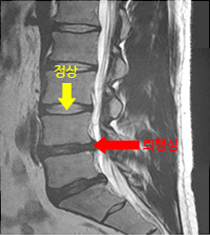

척추와 뼈 사이에 위치한 이 디스크는 외부로부터의 물리적 충격을 완화하고 단단한 뼈가 직접 충돌할 때 문제가 발생하지 않도록 하는 탄성이 높은 구조입니다. 외부의 영향이나 잘못된 위치로 인해 디스크가 꺼지면 염증이 발생하고 신경이 눌려 요통과 요통이 발생합니다. 기술적으로는 요추 디스크 분리라고 하며 일반적으로 요추 디스크 고장이라고 합니다.

디스크는 몸이 척추로부터 떨어져 많은 고통을 느낄 때까지 여러 단계를 거칩니다.